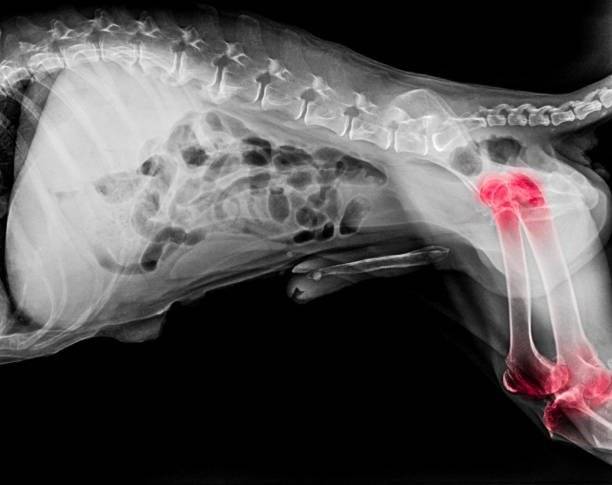

Enfin, l'arthrose peut théoriquement toucher quasiment toutes les articulations, mais dans la pratique, certaines sont plus fréquemment atteintes que les autres. Chez les chiens, elle se manifeste surtout au niveau des genoux, des hanches et des coudes.

Si c'est bel et bien de l'arthrose qui semble être en cause, il effectue ensuite une radiographie, une IRM et/ou un scanner pour confirmer le diagnostic.